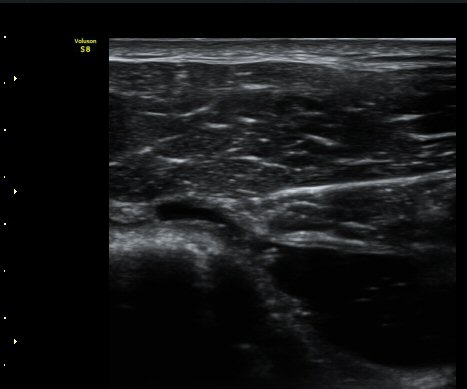

ŽÃÊÀÚ¸¦ ¾à°£ ´Ù¸®ÂÊ, ³»ÃøÀ¸·Î À̵¿ÇÏ´Ï °ß°©ÇÏ±Ù°Ç Ç¥Ãþ¿¡ ¸¹Àº ¾çÀÇ ¼ö¾×Àú·ù°¡ °üÂûµÈ´Ù(»çÁø 3).

ÆÈÀ» ¿ÜȸÀüÇÏ´Ï °ß°©ÇÏ±Ù°Ç Ç¥ÃþÀÇ ¼ö¾×Àú·ù°¡ ´õ¿í È®½ÇÇÏ°Ô °üÂûµµ´Ï´Ù(»çÁø 4).